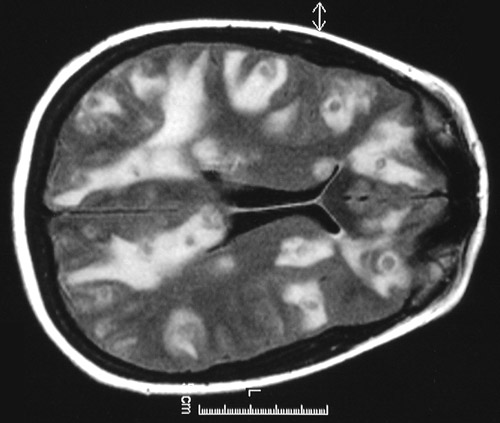

The T2 weighted MRI scan above and the FLAIR scan below demonstrate numerous brightly enhancing

ring enhancing abscesses

with prominent surrounding

edema

, which is bright on these scans. These are

Nocardia braziliensis

abscesses.